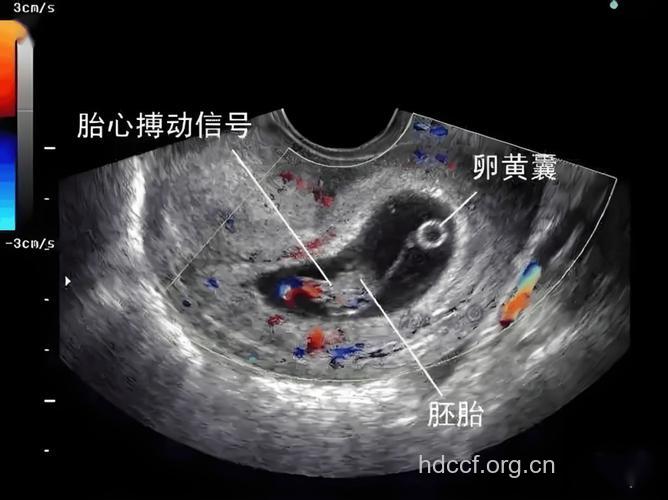

怀孕5周只要是能看到胎芽,那么就是可以排除葡萄胎的,因为葡萄胎是没有胎芽的,一般怀孕8周以内应该有胎心胎芽的,所以最好是等怀孕8周左右检查B超的。